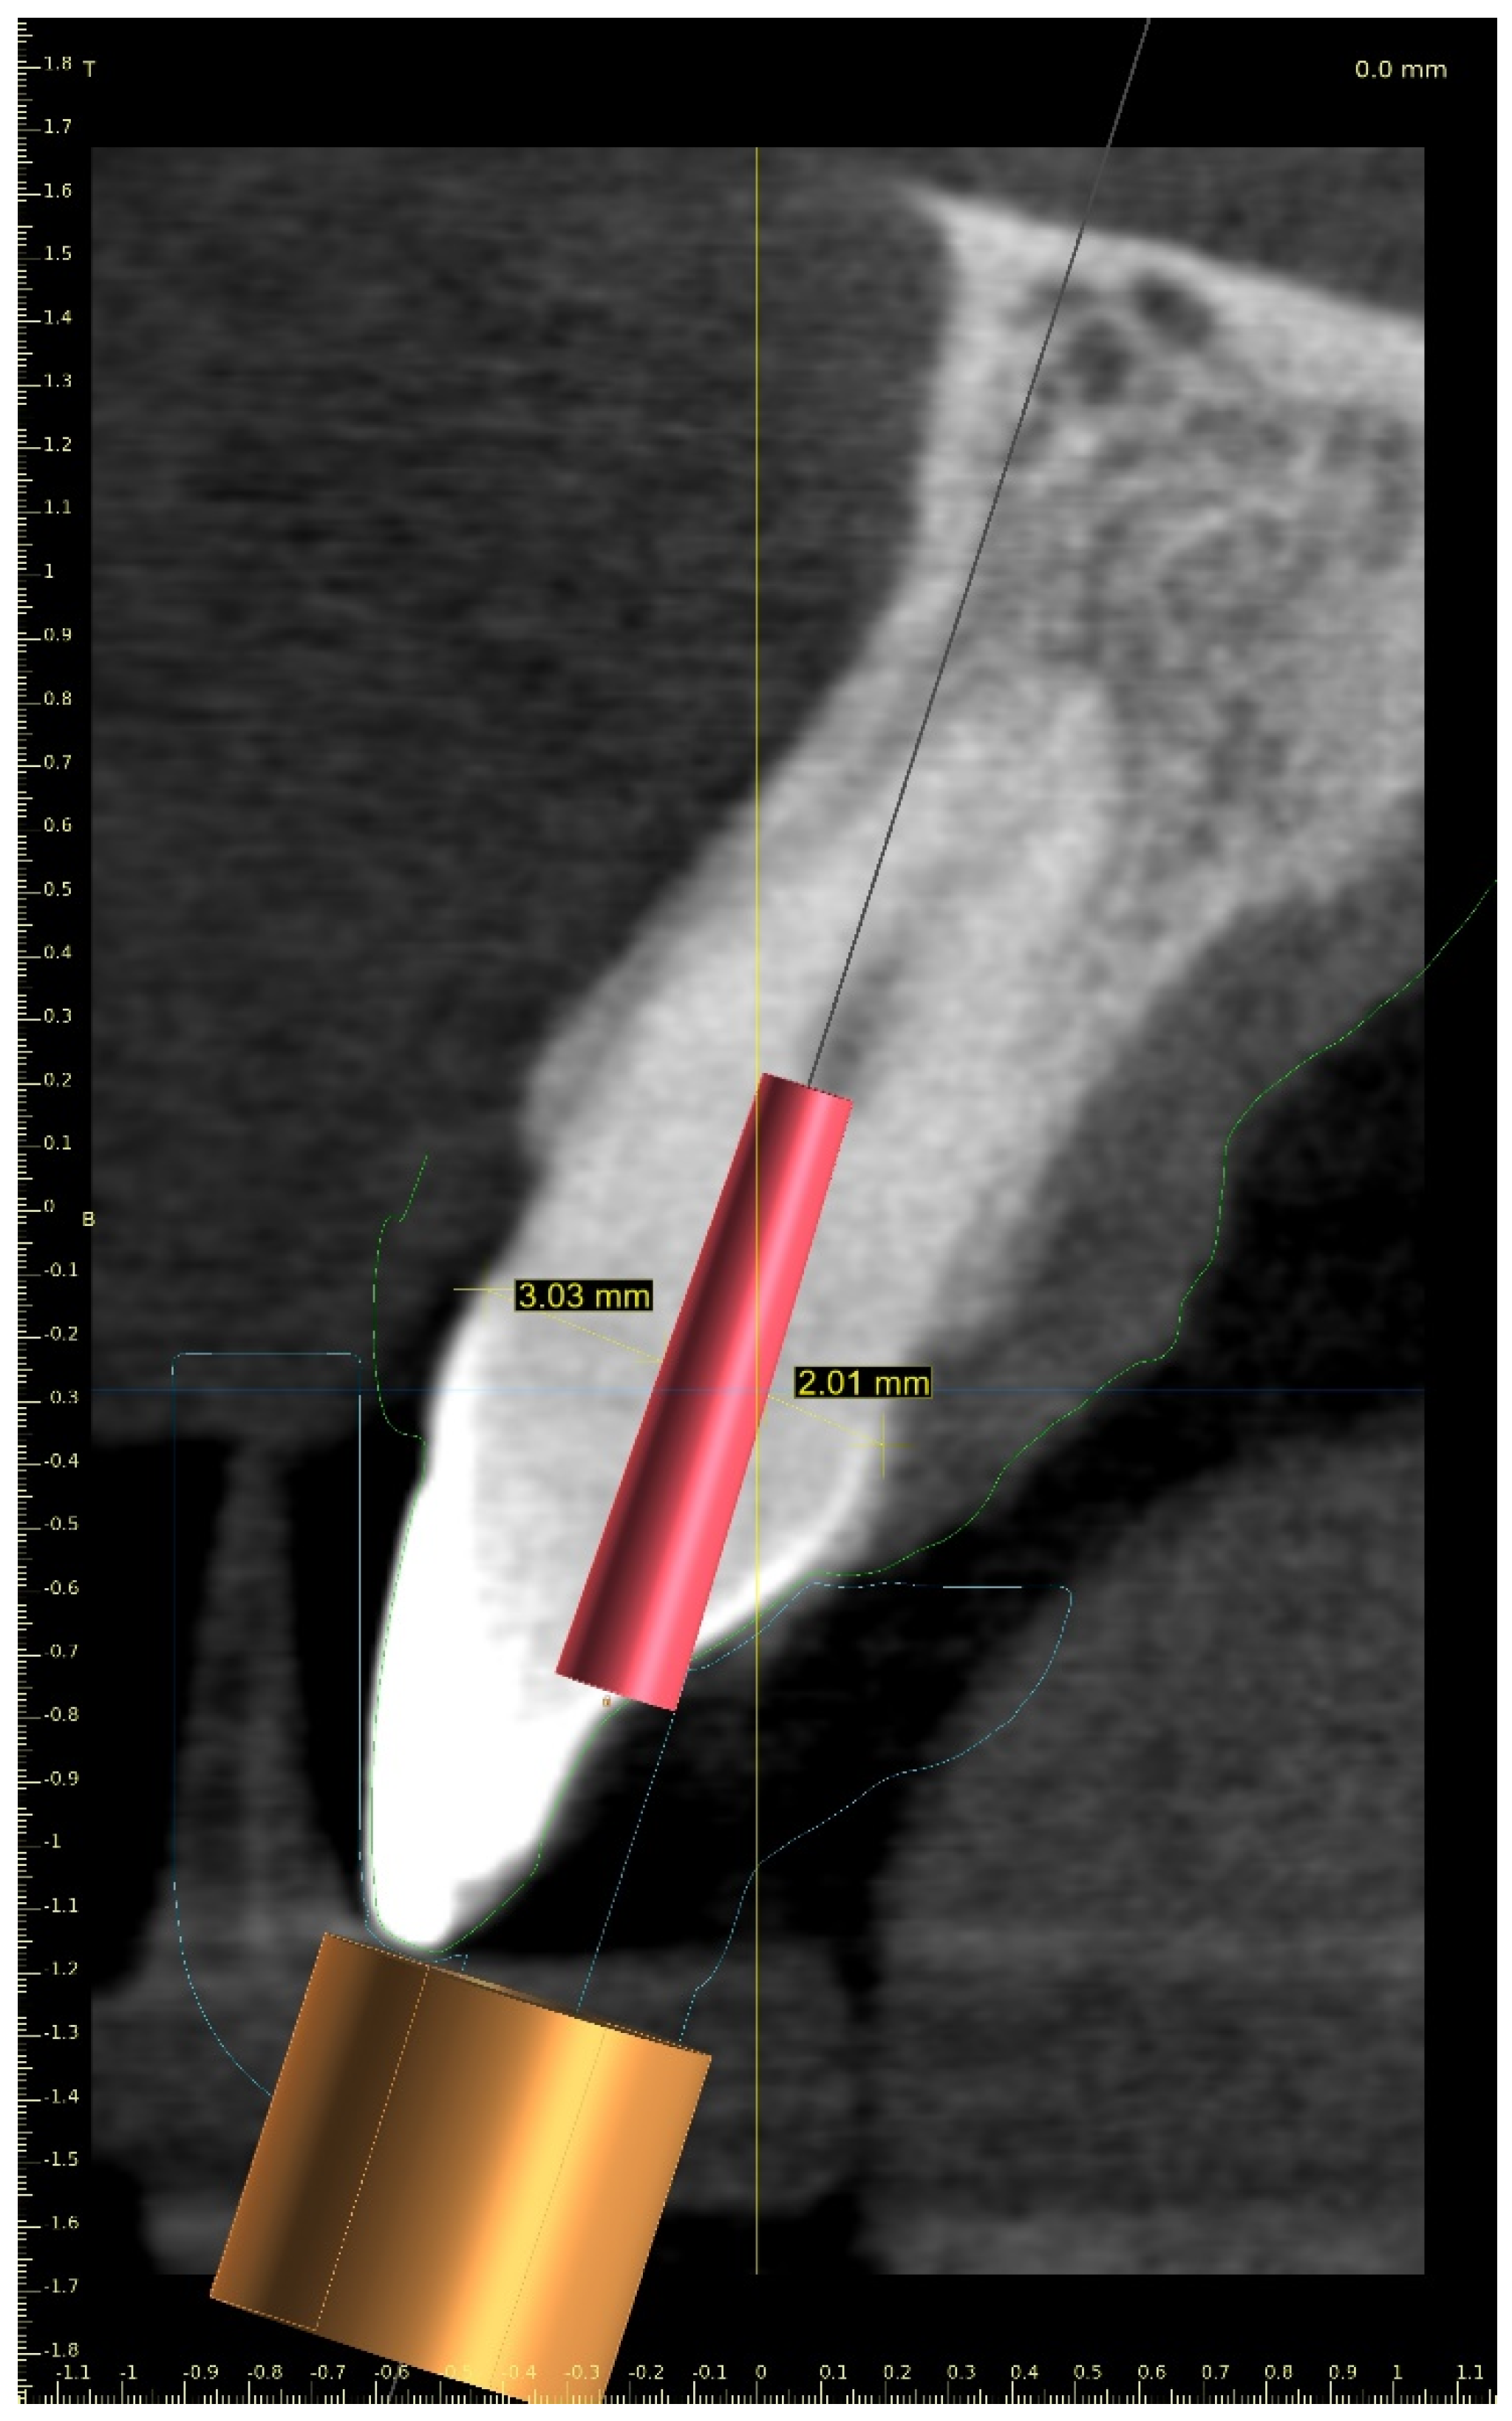

The upper arch was scanned with an intraoral scanner (PrimeScan, Dentsply Sirona) instead of analogue impressions. The STL file of the upper arch and the CBCT images were combined in Blue Sky Plan (Blue Sky Bio). The accuracy of the merging was cross-checked in three dimensions (Figure 9). An individual virtual implant with a diameter of 1.5 mm was used during planning, in accordance with the diameter of the endodontic access tool (Figure 10). The CBCT images allowed us to plan the position of the virtual implant so that the drill apex was located at the top of the visible part of the root canal system [23] (Figure 11).

Figure 10. Figure presenting settings of custom implant in Blue Sky Plan software. Implant length, guide tube height, and offset must be equal to access tool’s working length.

Figure 11. CBCT image presenting a scheduled virtual implant: endodontic access path in (a) sagittal view and (b) coronal view. The volume of the preserved dentin around the access path is shown.